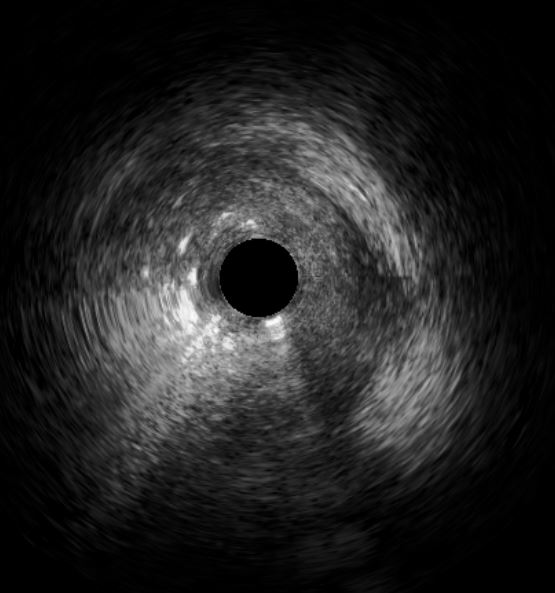

Initial engagement with a JR3.5/6Fr guiding catheter provided suboptimal support; this was switched to a SAL 0.75/6Fr guide, which offered only modest improvement. Lesion predilatation was performed with non-compliant balloons (0.85/15 mm and 1.5/15 mm) assisted by a guide extension catheter. Intravascular ultrasound (IVUS)revealed a distal reference vessel diameter of 3.0 mm and proximal reference of 3.5 mm, with evidence of white thrombus at the mid RCA. Further lesion preparation was performed using Naviscore balloons (3.0/15 mm distally and 3.5/15 mm proximally),achieving satisfactory luminal gain. A repeat IVUS run confirmed resolution of the white thrombus. Based on this, a drug-coated balloon(DCB)-only strategy was chosen. EssentialPro DCBs (2.0/40 mm for distal-mid segment, and 3.5/40 mm for mid-proximal segment) were successfully delivered and deployed. Post-procedure IVUS demonstrated significant improvement in minimum lumen area (MLA)—from 2.91 mm©÷to 4.07 mm©÷ (distal) and 1.60mm©÷ to 6.93 mm©÷ (proximal).